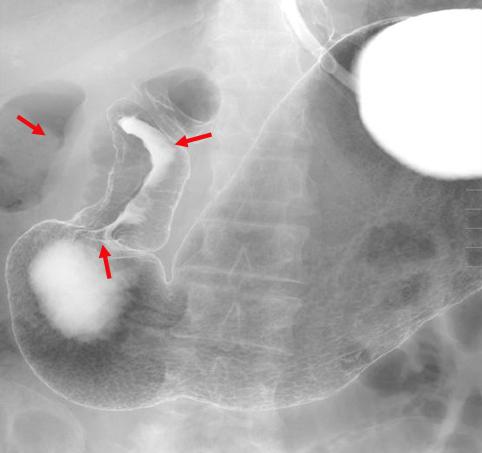

A case of type 5 advanced gastric cancer which developed in the antrum and was diagnosed by multidisciplinary method.

[ Image ID:11374 ]

Malignant epithelial tumor/Adenocarcinoma

Stomach/Antrum

X-ray

Type 5 Unclassfied type/

40 -

serosa (adventitia)